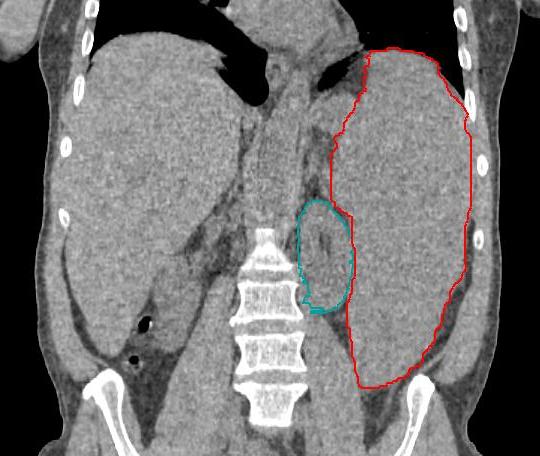

말초혈액검사 및 혈액 도말 검사를 포함한 전형적인 진단 검사들을 통해 혈액 도말 형태는 용혈성빈혈, 가성 혈소판감소증으로 이어지는 혈소판 응집 또는 백혈병에 대한 단서를 제공받을 수 있다.[34] 또한, 루푸스(전신성 홍반 루푸스), 간염, B12, 엽산 또는 기타 비타민 결핍, 신부전 또는 심부전, HIV, 용혈성빈혈, 단일클론 감마병증 등 혈구감소증의 다른 일반적인 원인을 배제하기 위한 혈액 검사도 진행한다. 모든 빈혈 환자에게 연령에 적합한 암 검진을 고려해야 한다.[34]

혈액병리학자에 의한 골수 검사는 필수적이다. 모든 혈액병리학자는 이형성 골수를 골수이형성증후군의 주요 특징으로 간주하기 때문이다.[35] 세포유전학 또는 염색체 연구는 이상적으로는 골수 천자액에서 수행된다. 살아있는 세포가 중기에 들어가도록 유도하여 염색체를 관찰할 수 있도록 하기 때문에 기존 세포유전학에는 신선한 검체가 필요하다. 간기 형광제자리부합법 검사는 기존 세포유전자 검사와 함께 진행되며 del 5q, −7, +8 및 del 20q를 포함한 MDS와 관련된 여러 가지 염색체 이상을 신속하게 검출한다. 또한, MDS에 대해 가상핵형 분석을 수행할 수 있다.[36] 이 방법은 계산 도구를 사용하여 손상된 DNA로부터 핵형을 구성하며, 세포 배양이 필요하지 않고 기존 세포유전학보다 해상도가 훨씬 높지만 균형전좌는 검출할 수 없다. 유세포 분석은 아형성구, 비정상 골수 성숙 및 골수에 림프증식성 질환이 있는지 여부를 확인하는 데 도움이 된다.

일반적으로 MDS를 정의하는 데 사용되는 특징은 혈구감소증, 비효율적인 조혈, 이형적혈구증, 이형과립구증, 이형거대핵판구증 및 골수아세포 증가이다. 이형성은 골수에서 관찰되는 세 가지 계열 모두에 영향을 미칠 수 있다.

이형성을 진단하는 가장 좋은 방법은 골수 천자액과 말초 혈액 도말에 사용되는 형태 및 특수 염색(PAS)이며, 골수계열의 이형성은 다음과 같이 정의된다.